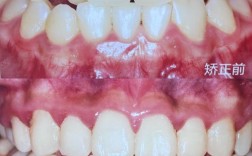

牙齿的核心功能是咀嚼,而咀嚼效率直接影响营养吸收——这是健康的“第一道关卡”,牙齿拥挤、错位会导致清洁困难,食物嵌塞引发龋齿、牙周炎,长期甚至可能引发消化系统疾病,深覆合可能造成下颌关节紊乱,导致头痛、张口受限;开颌则影响咬合效率,让食物无法被充分磨碎,据《中国口腔健康指南》数据,我国70%以上存在错颌畸形,其中30%因未及时矫正,引发了继发性健康问题。

矫正通过移动牙齿、调整颌骨关系,本质上是在重建口腔的“生态平衡”,牙齿排列整齐后,刷牙效率提升90%以上,龋齿、牙周病风险显著降低;咬合功能恢复,咀嚼效率提高,肠胃负担减轻;甚至对呼吸、睡眠(如改善睡眠呼吸暂停)也有间接帮助,当一个人不再因牙痛频繁就医,不再因消化不良影响精力,健康这个“人生地基”稳固了,才有更多精力去追求事业、经营生活——这是矫正带来的最基础却最关键的“命运改变”。